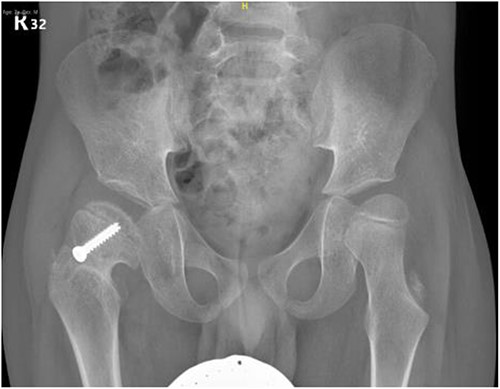

A 5-year-old independent ambulatory Middle Eastern boy with CP who was born preterm and developed grade III intraventricular haemorrhage and periventricular leucomalacia and was on AEDs, including valproic acid (VPA) and levetiracetam (LEV), for >3 years and was controlled over the last year (no history of seizure attack) presented to the emergency room (ER) with right hip pain and inability to bear weight for 4 weeks; the patient had no history of fever or trauma. Physical examination shows a thin, the weight is 12 kg, the height is 101 cm, vital signs within the normal range, tenderness over the right hip, and external rotation of the right hip, with restricted hip mobility. A radiological study was performed ~3 months before the patient presented to the ER for follow-up examination of a left hip coxa valgus deformity with no apparent abnormalities in the right hip (Fig. 1). Initial imaging studies conducted in the ER showed an anterior–posterior view of the pelvic radiograph, revealing Klein’s line [13] not intersecting the capital femoral epiphysis (Fig. 2), and frog-leg lateral view radiograph of the right hip (Fig. 3) confirmed SCFE and Southwick’s slip angle [13] of ~50° (moderate). Laboratory findings were clear for endocrine and renal diseases or infection, except for low vitamin D (total 25-OH Vitamin D: 43.4 nmol/L), suggesting vitamin D insufficiency. The diagnosis was confirmed with clinical and radiological studies as right-sided unstable SCFE requiring surgery. Surgical intervention was performed with percutaneous in situ fixation using a single fully threaded 4.5-mm cannulated screw (Fig. 4). Postsurgical rehabilitation included non-weight-bearing right lower extremities for 6 weeks. Regular follow-up with serial radiology studies showed stable fixation with no migration of screw or further slippage at 6 weeks (Fig. 5) and 3 (Fig. 6), 15 (Fig. 7), and 36 months (Fig. 8). During follow-up, a painless range of motion in the right hip was observed, with full weight-bearing and resumption of his usual activities with no complaints.

Pelvic anterior–posterior radiograph showing coxa valga deformity in the left hip.